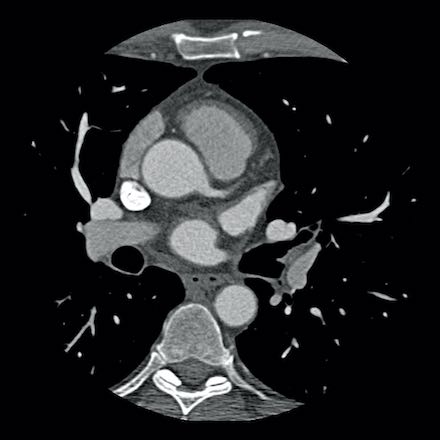

case 3 – Calcium score 0 and severe stenoses.

First, scroll through the CTA images.

How would you describe the findings on the coronary CTA?

The findings are:

- The total calcium

score of 0 indicates the absence of calcified plaque in the coronary

tree. - Severe stenosis

(70-99%) in the mid LAD and D2 branch.

Continue with the next images of the same patient…

Same patient. First, study the CTA image.